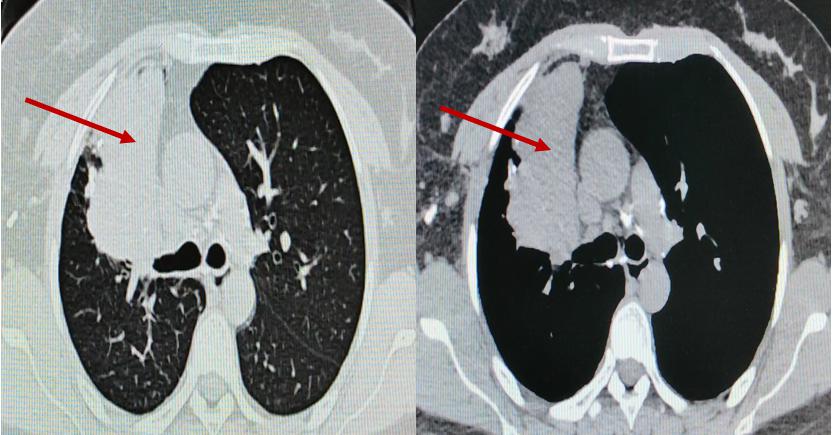

▲术前胸部CT

患者为36岁女性,既往有肺结核病史,近两年反复出现低热、咳嗽症状,胸部CT提示右肺上叶大片实变、坏死及多发黏液栓,气管镜显示支气管瘢痕性闭塞,化验提示曲霉菌感染。患者曾接受长期口服抗真菌药物治疗,但病灶未缩小,并出现视神经损害等药物并发症,停药后病情仍反复,右肺出现新发病灶。

入院后,呼吸与危重症医学科介入团队对患者病情进行全面评估。完善胸部增强CT提示:右肺上叶大片状实变并坏死,支气管完全闭塞。由于前期单纯口服抗真菌药物效果不佳,因此联合气管镜下介入治疗势在必行。经过认真评判,团队制定了详细的气管镜下介入诊疗计划。治疗过程包括:超声支气管镜引导下精准穿刺,高频电刀微创开窗建立引流通道;钳夹清除远端大量坏死组织;局部灌注抗真菌药物以提高病灶药物浓度;结合球囊扩张与超细冷冻冻融治疗,扩大引流窗口;并多次行镜下冲洗,彻底清除分泌物与坏死物。

经过系统治疗,患者低热症状消失,精神状态逐步好转。术后气管镜复查显示右上叶前段闭塞支气管已重新开放,坏死物基本清除;胸部CT显示原新发病灶消失,前段病灶引流通畅,炎症吸收良好,成功保留了右肺功能。